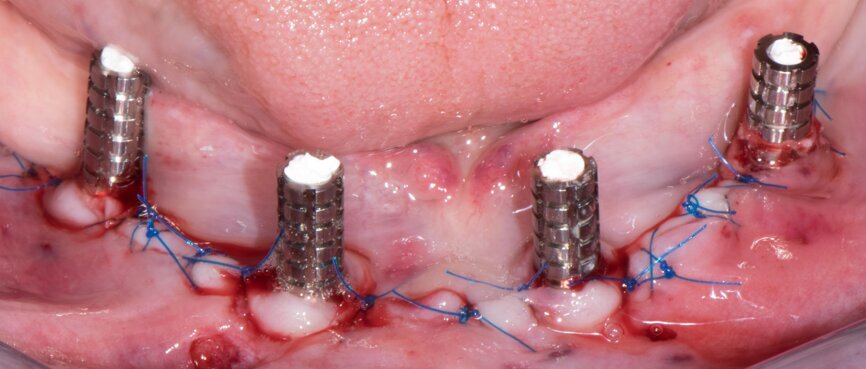

Implant beds were prepared (Figs. 13 & 14) and Straumann BLT implants placed with a torque setting of more than 35 Ncm, following the protocol to allow correct subsequent screw retained abutment placement (Figs. 15 & 16). Bone around the implants was prepared with bone profilers (Straumann) for the same reason (Fig. 17). The crest was flattened (Figs. 18 & 19), screw-retained abutments were screwed to 35 Ncm (Fig. 20) and covered with healing caps, and the wound was sutured (Fig. 21).